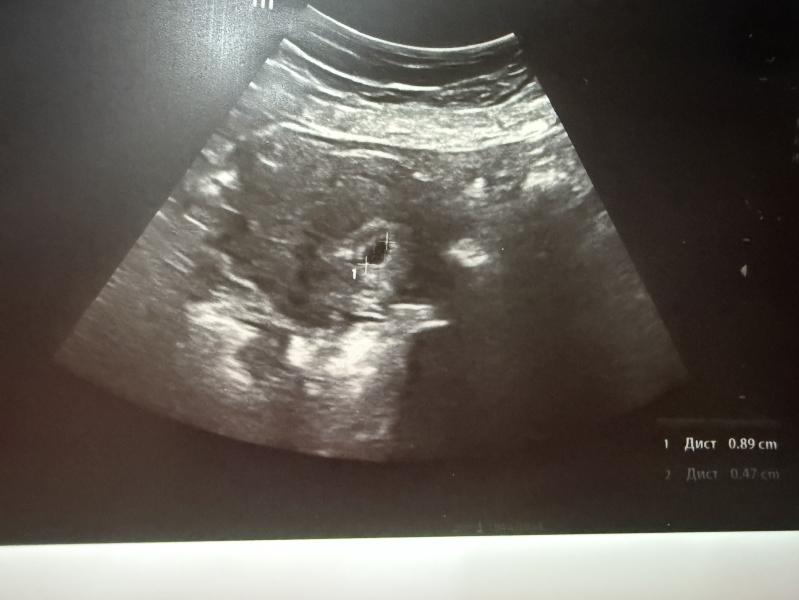

Была сегодня на узи , эмбриональный срок 3 нед (поздняя овуляция, для меня это норм ), ПЯ выросло за 5 дней на 5мм, все отлично , смотрели абдоминальным датчиком , потому что, внутрь лишний раз лучше не лазить , сказал врач , через пару недель контроль и на учет 😌🙃